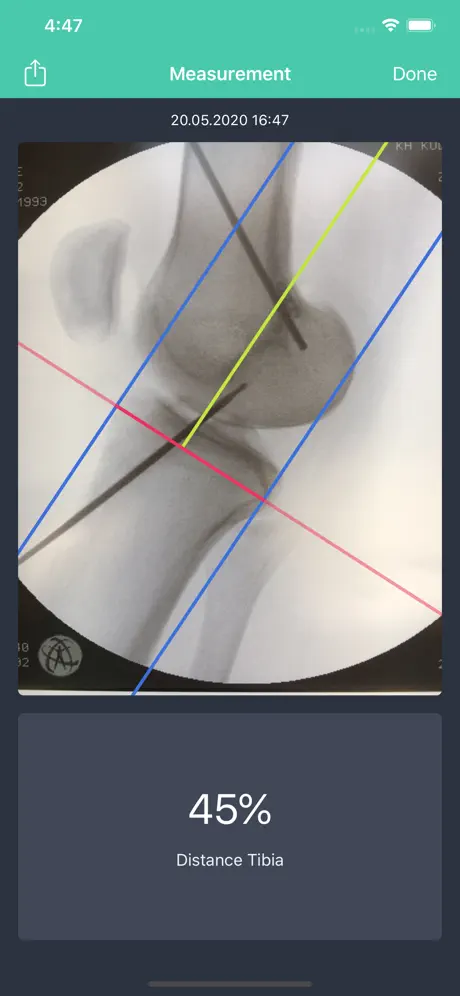

Tibia measurement of a radiographic image has been described by Stäubli und Rauschning. It may help knee surgeons identify the ideal position of the tibial bone tunnel during ACL reconstruction.

Place a guide pin into the center of the projected tibial bone tunnel using a drill guide in a normal fashion. The guide pin may intrude the joint beyond the cortical edge of the ACL footprint.

This app will display the relative distance (in percent) of the entry point of the guide wire into the joint in relation to the total anterior posterior (AP) distance of the proximal tibia (100 %).

Tibia measurement of a radiographic image has been described by Stäubli und Rauschning. It may help knee surgeons identify the ideal position of the tibial bone tunnel during ACL reconstruction.

Place a guide pin into the center of the projected tibial bone tunnel using a drill guide in a normal fashion. The guide pin may intrude the joint beyond the cortical edge of the ACL footprint.

This app will display the relative distance (in percent) of the entry point of the guide wire into the joint in relation to the total anterior posterior (AP) distance of the proximal tibia (100 %).